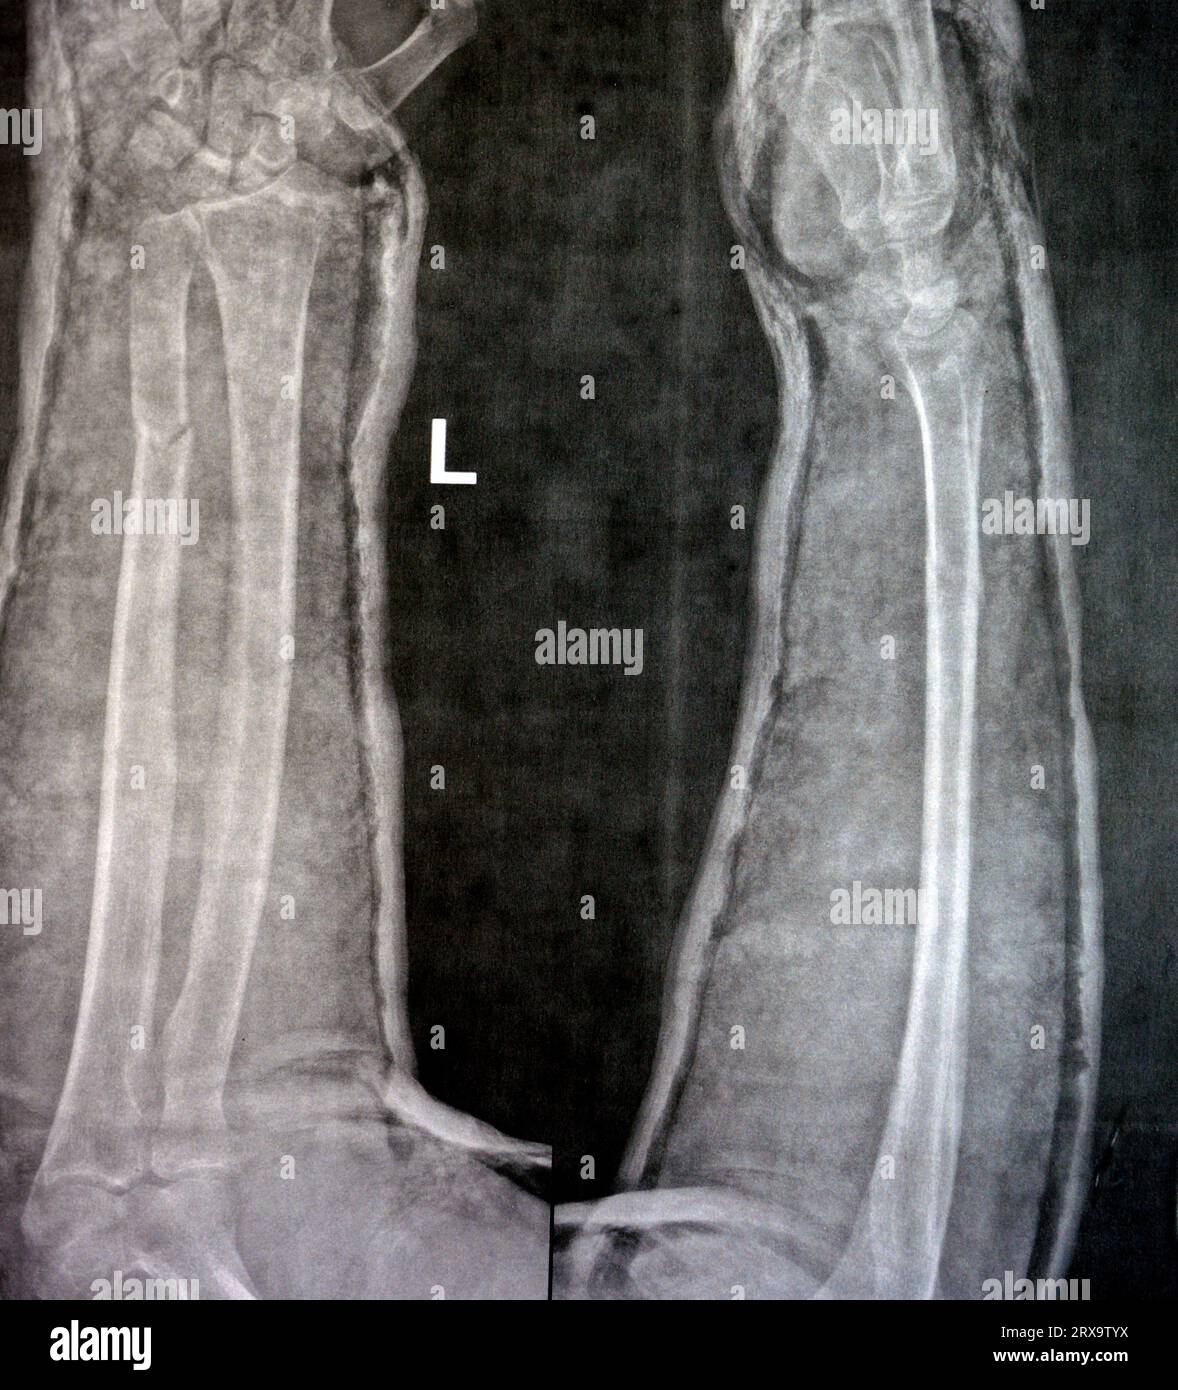

From www.alamy.com

Fracture shaft of ulnar bone ( forearm bone ) ( Left pretreatment Broken Ulna Cast How to apply a cast for forearm fractures. The forearm bones (radius and ulna) are the two most commonly broken bones in the. It can take longer if your arm or wrist was severely damaged. A distal ulna fracture, or isolated ulnar shaft fracture, is a type of fracture that occurs along the length of the ulna bone, which is. Broken Ulna Cast.